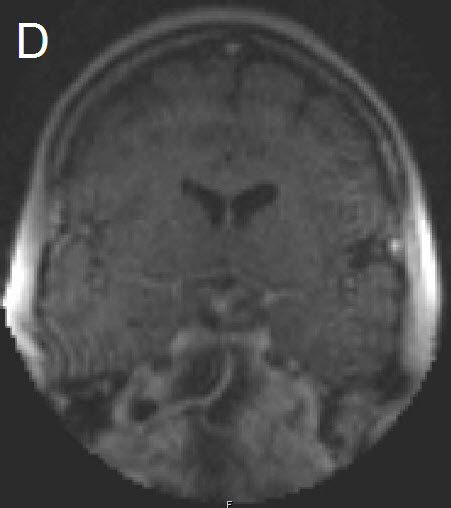

Figure 1 Illustrative case: Preoperative, intraoperative and postoperative imaging. A: Preoperative MRI, coronal view, contrast enhanced. B: Intraoperative MRI, coronal view, contrast enhanced, before skin incision. C: Intraoperative MRI, coronal view, contrast enhanced, during resection. D: Intraoperative MRI, coronal view, contrast enhanced, before closure. E: Postoperative MRI, coronal view, contrast enhanced.

A forty-two year old female was admitted for resection of a large pituitary adenoma. She complained about headache, amenorrhea and galactorrhea. Endocrinological diagnosis revealed a panhypopituitarism. The patient underwent surgery and the non-functioning pituitary adenoma could be totally removed. Postoperative follow-up showed normal pituitary function and the patient has now been in remission for 48 months. The figures show preoperative imaging, intraoperative imaging with various stages of the tumour resection, and postoperative follow-up MRI.